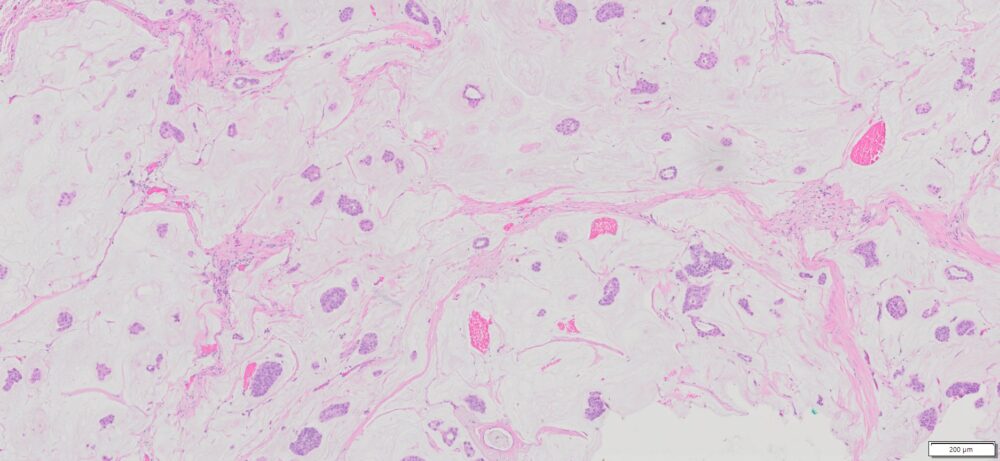

| HuPS-02040T1 | Breast | Adenocarcinoma | No | Female/64 | 25% | II | NA | NA |

Human tissue was fixed in formalin immediately after excision and embedded in paraffin. The tissue sections were 5 µm in thickness and mounted each on positively charged glass slides.